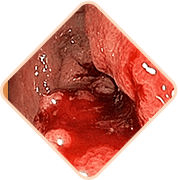

Sangrado durante la defecación

o rastros de sangre en las heces

Prolapso hemorroidal

Sensación de cuerpo extraño y

pesadez

Sensación de picor y

quemazón en el ano

Dolor al defecar,

caminar o sentarse

Sensibilidad al tacto de

los nódulos hemorroidales